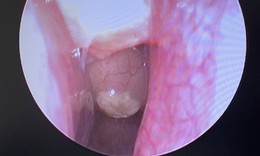

Nội soi gắp dị vật là vòng bạc trong dạ dày bé gái 5 tuổi

Y tế - 09/10/2025 18:30SKĐS - Mới đây, Bệnh viện Việt Nam – Thụy Điển Uông Bí tiếp nhận và xử trí thành công trường hợp trẻ 5 tuổi nuốt phải dị vật là chiếc vòng tay bằng bạc, dài khoảng 7 cm.